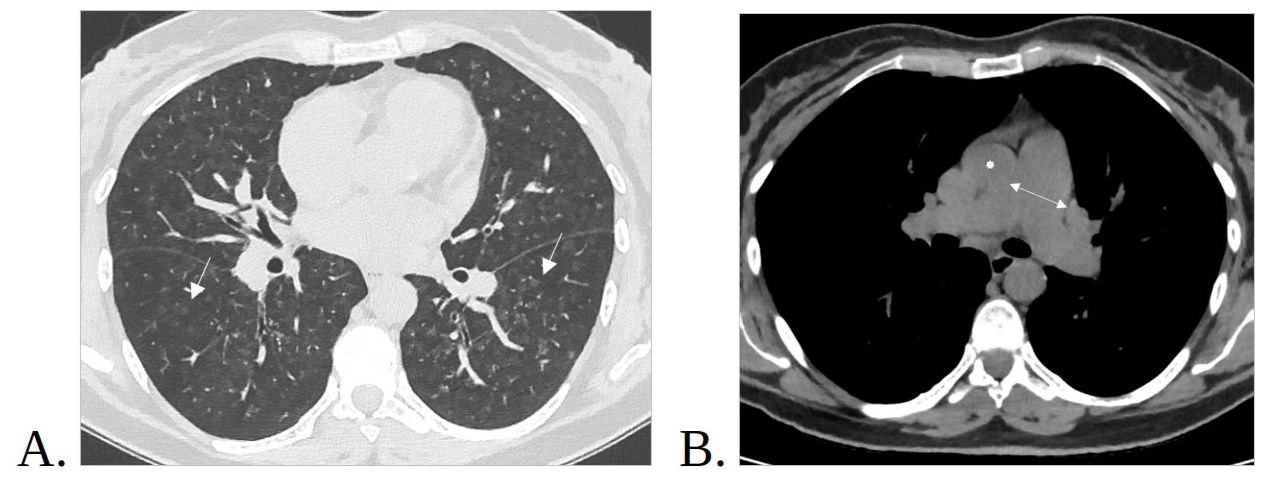

2. Рис.2 МСКТ органов грудной клетки, аксиальная проекция. | |

4. Рис.4. МСКТ органов грудной клетки, аксиальные срезы. | |